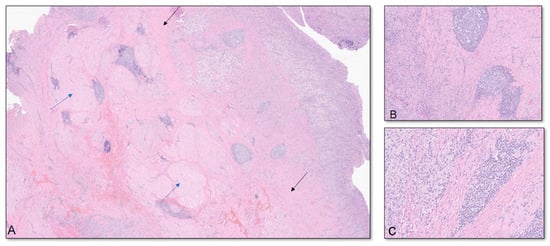

Six months after the booster, the patient discovered a mass in the anteromedial right upper arm. He reported 3-out-of-10 pain in his right arm, but his main concerns were limited range of motion (ROM) attributed to a feeling of “heaviness” and his concern of a possible malignancy. The lump was described as a solid, “golf-ball-sized” mass without induration, warmth, discoloration, or urticaria. Four days after noticing the mass, he consulted his primary care physician, who ordered a magnetic resonance imaging (MRI) of his right arm that showed a 7.4 × 3.7 × 2.6 cm mass in the short head of the right biceps with mild hemorrhagic fluid abutting the humerus but with no evidence of cortical erosion or bone marrow signal change (Figure 1).

Figure 1. Multiplanar MRI of the right upper arm taken five days after identifying the mass and six months after receiving the booster dose. Axial T2 (A) and coronal T1W FS (B) images show an ill-defined fluid signal within the short head, right biceps muscle belly. The area involved extended from the muscle belly to the proximal humeral cortex, measuring approximately 7.4 × 3.7 × 2.6 cm (arrows).